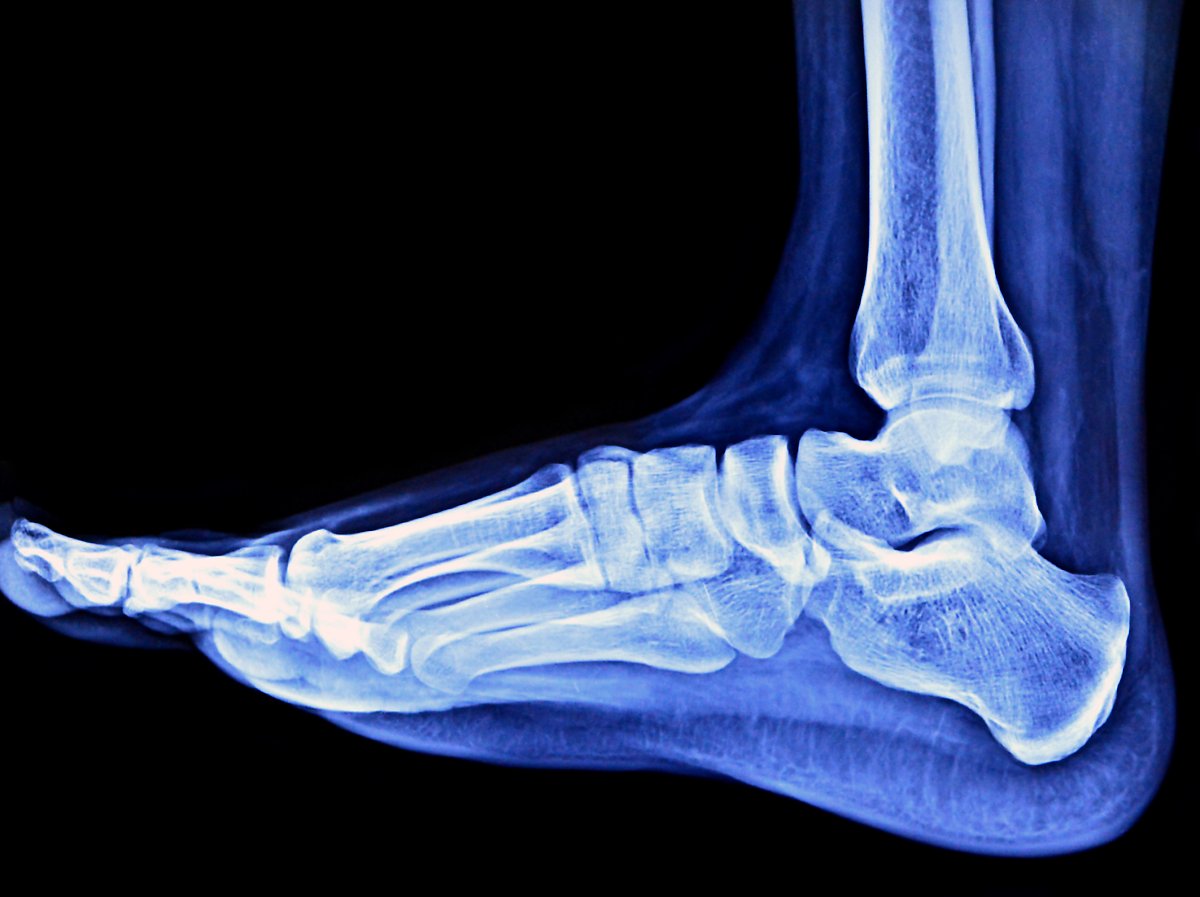

골절 여부는 신체 검진과 단순 방사선 촬영(x-ray)을 통해 판단합니다. 만성 불안정성이 의심되면 발목에 스트레스를 가한 뒤. 단순 방사선 촬영으로 인대 손상을 유추할 수 있습니다. 간혹 동반된 기타 연조직 손상 정도와 인대의 파열 정도를 정확하게 파악하고자 MRI 등의 검사를 진행하기도 합니다.